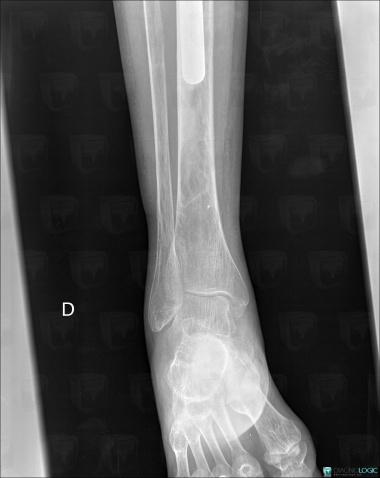

Avascular necrosis, Tibia - Distal part, X rays

Here is the specific information in the key image above:

- Diagnosis Avascular necrosis, Location(s) Tibia - Distal part, with gamuts Well-defined osteolysis

Avascular necrosis, Talus, Calcaneus, X rays

- Diagnosis Avascular necrosis, Location(s) Calcaneus, with gamuts Lucent lesion in footTalus, with gamuts Lucent lesion in foot